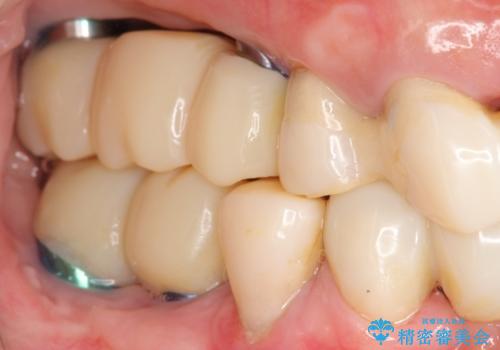

歯周病 全顎治療

- 前歯の見た目、入れ歯による噛めないことの改善を求めて来院されました。

検査により全顎的な歯周病治療、欠損のインプラント補綴、根管治療が必要な状態であることをお伝えし、治療を計画します。